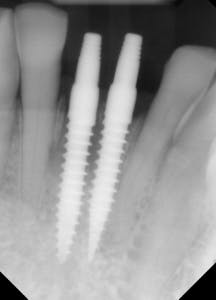

This patient presented with discomfort and mobile teeth Nos. 24 and 25. Extractions were performed, and the area was allowed to heal for six months. Mini-implants were placed in site Nos. 24 and 25 and immediately loaded with temporary crowns. The final splinted restoration was cemented two weeks later.

Figure 8: Initial implant placement DIO 3.0 x 16 mm implants